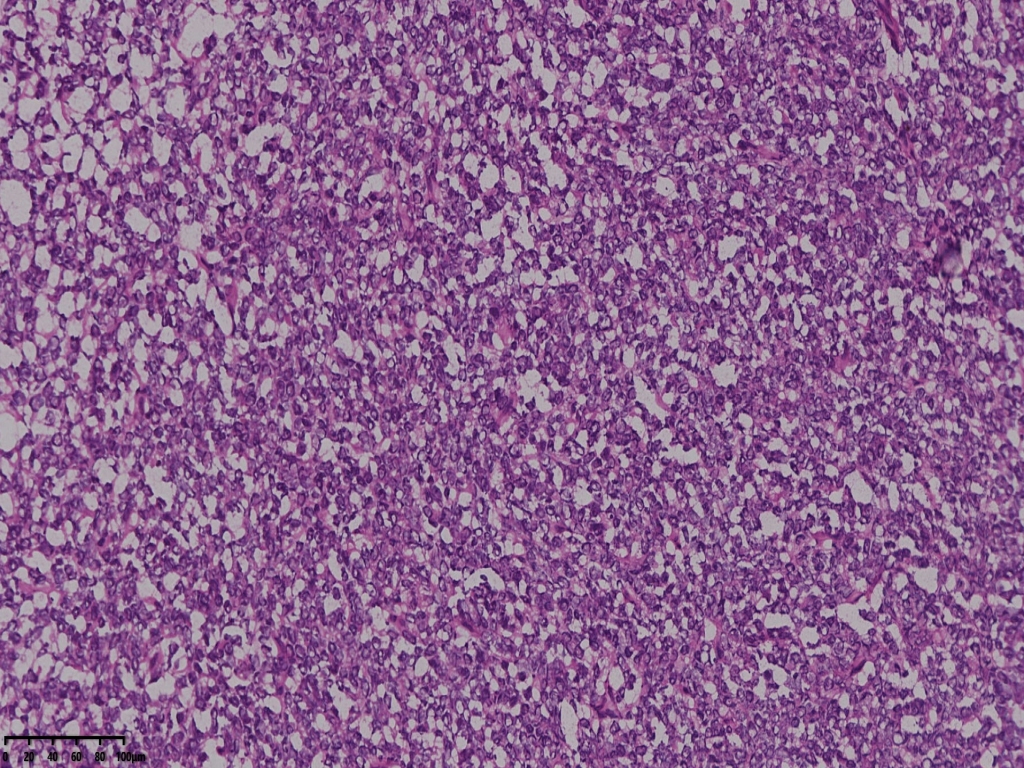

冰冻切片取两块实性区组织,其中1块可见梭形细胞为主,另一块似上皮样细胞,细胞丰富密集。

术中考虑卵巢性索间质来源肿瘤,待石蜡及免疫组化。

考虑颗粒细胞瘤。